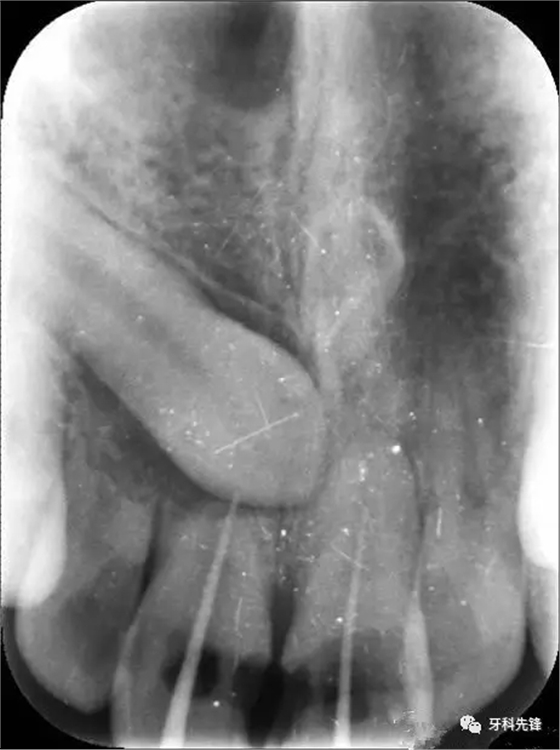

圖1.術前的根尖片影像:12、11根尖2/3壓迫吸收、11、21根管內(nèi)各有一牙膠尖。